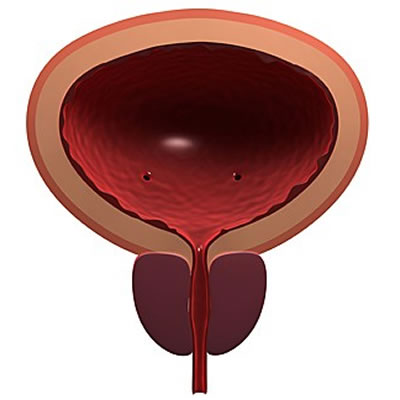

Esse aparelho substitui a função do esfíncter natural, um músculo em forma de anel que envolve a uretra e controla a liberação da urina. Como ele fica quase "grudado" na próstata, pode acabar enfraquecido após a cirurgia.

Segundo o urologista Carlos Sacomani, do Hospital A.C. Camargo, entre 5% e 10% dos indivíduos que retiram totalmente essa glândula – exclusiva do sistema reprodutor masculino, localizada abaixo da bexiga e responsável por armazenar um fluido que compõe o sêmen – apresentam algum tipo de perda involuntária de urina, que pode ser leve, moderada ou grave.

Esse aparelho substitui a função do esfíncter natural, um músculo em forma de anel que envolve a uretra e controla a liberação da urina. Como ele fica quase "grudado" na próstata, pode acabar enfraquecido após a cirurgia.

Segundo o urologista Carlos Sacomani, do Hospital A.C. Camargo, entre 5% e 10% dos indivíduos que retiram totalmente essa glândula – exclusiva do sistema reprodutor masculino, localizada abaixo da bexiga e responsável por armazenar um fluido que compõe o sêmen – apresentam algum tipo de perda involuntária de urina, que pode ser leve, moderada ou grave.